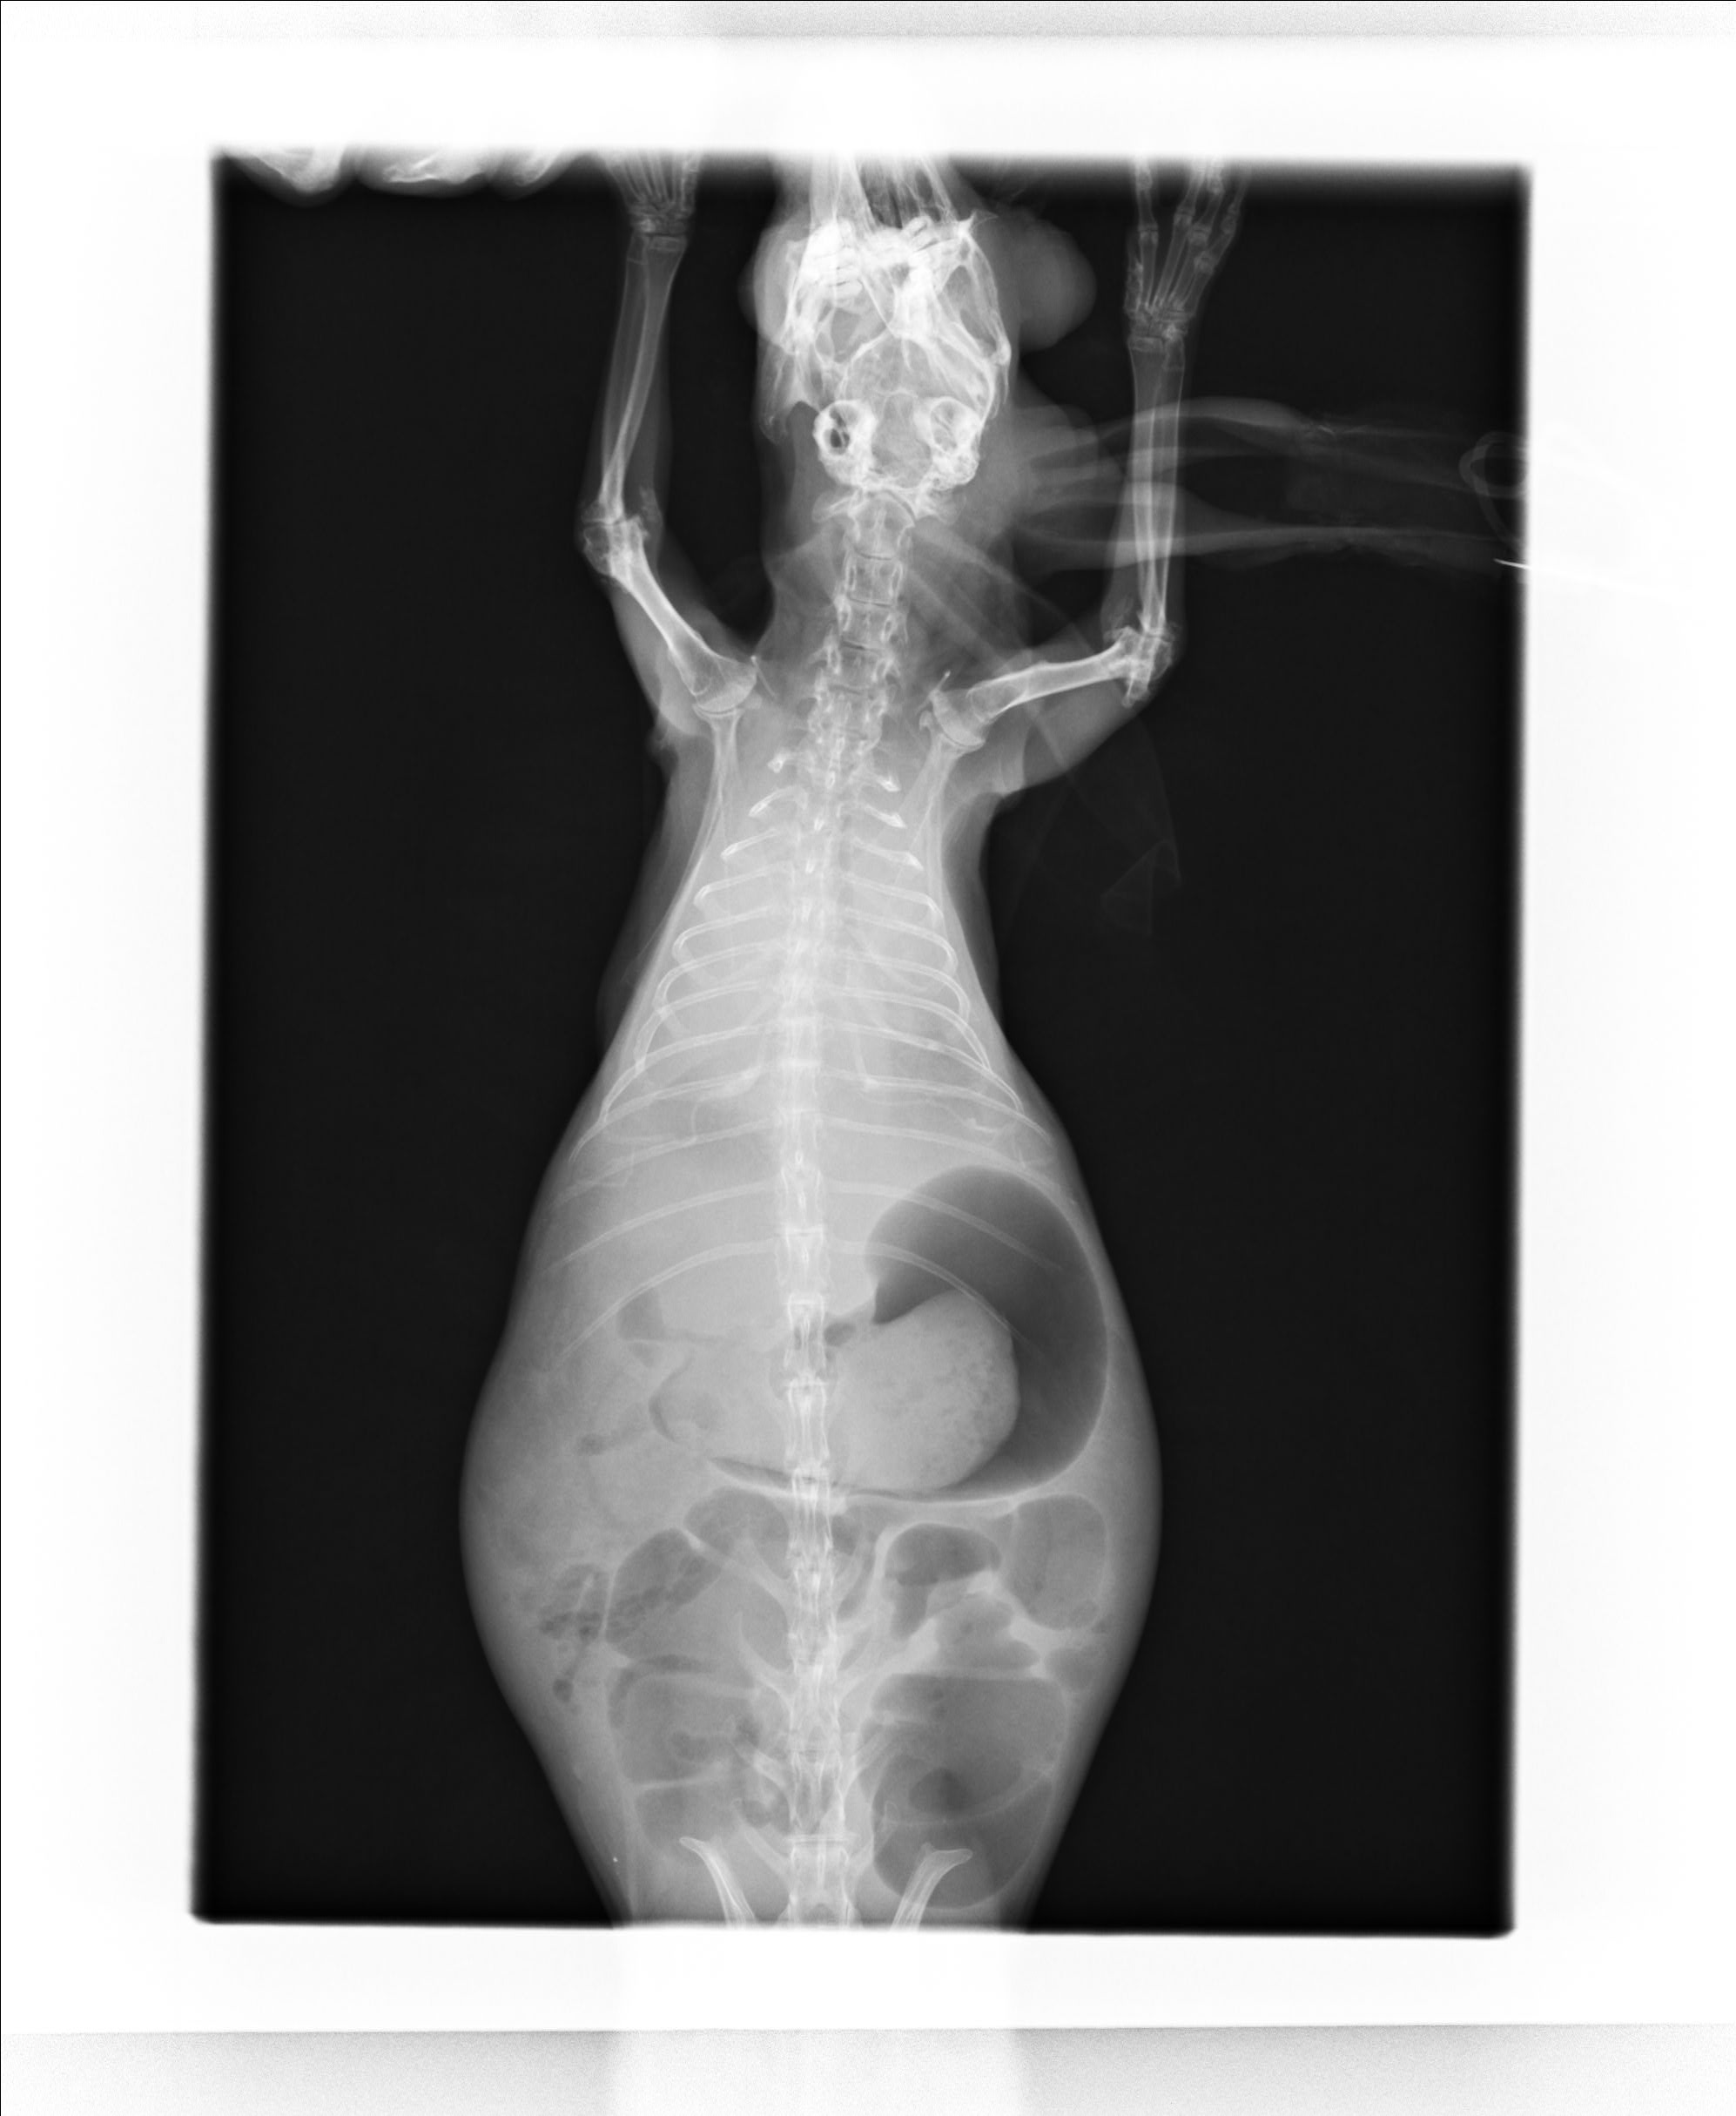

診断は臨床症状に加え、画像検査によって行います。X線検査や超音波検査により胸腔内の腫瘤性病変として認識されることが多いですが、胸腺腫や縦隔リンパ腫との鑑別が困難な場合があります。画像上では境界明瞭な腫瘤として描出されることがあり、単独の画像所見のみでの確定診断は難しいことがあります。必要に応じて細針吸引や生検を行い、細胞診や細菌培養により診断を補助します。

症例:8歳 ホーランドロップ 未避妊メス

3日前から食欲ないとの主訴で来院。検査では腎臓が悪く、肺に腫瘤が認められたため、抗生物質、ステロイドによる治療を行いましたが治療の甲斐なく亡くなってしまいました。この子のヒストリーでは胸腺腫、子宮腺癌の肺転移、肺膿瘍などが考えられましたが、呼吸状態と腎臓も悪く生前に積極的な検査を行うことができませんでしたが、肺の細胞診で肺膿瘍が疑われました。